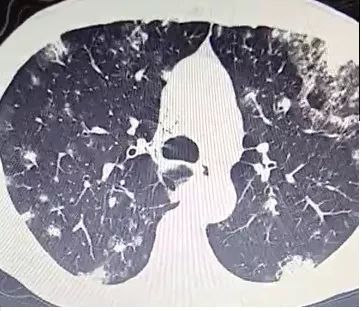

下面这个CT,乍一看,是不是毫无头绪?

然而,当病人说每天咳痰两三碗,大约200~300ml(1市斤500ml),而且是经常这样的时候,我突然眼前一亮,莫非是?

抗感染治疗,痰量增多。CT如下,没有什么特殊的。

■ 北京大学第一医院呼吸内科报道1例,每天咳痰多达500ml,外院抗感染治疗无效。给予靶向药吉非替尼治疗,痰量减少。CT如下,没有什么特殊的。